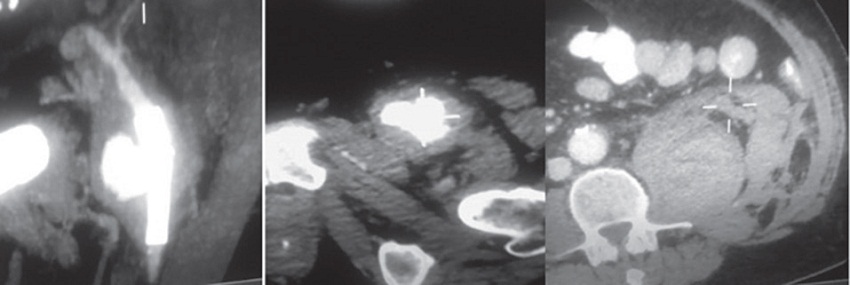

Al noveno día presentó súbitamente hipotensión arterial y dolor en fosa ilíaca izquierda, asociado a caída de 8 puntos del hematocrito. La angiotomografia evidenció ruptura contenida de pseudoaneurisma de arteria femoral común izquierda, a nivel del sitio de implantación del wallstent, con hematoma retroperitoneal de 15 × 7,5 cm. (Figura 1) De urgencia, por acceso percutáneo femoral contralateral, se procedió a implantar stent graft auto expandible (Viabahn®) de 7 × 50 mm, por dentro del wallstent que se encontraba permeable e indemne, con evidencia de extravasación de contraste por ruptura de la pared arterial. (Figura 2) El paciente evolucionó afebril, con hemocultivos negativos y eco Doppler cardíaco sin vegetaciones; cumplió 15 días de tratamiento antibiótico endovenoso y luego recibió ciprofloxacina 750 mg c/12 horas vía oral hasta completar 6 meses. Se encuentra asintomático en el seguimiento a 2 años.